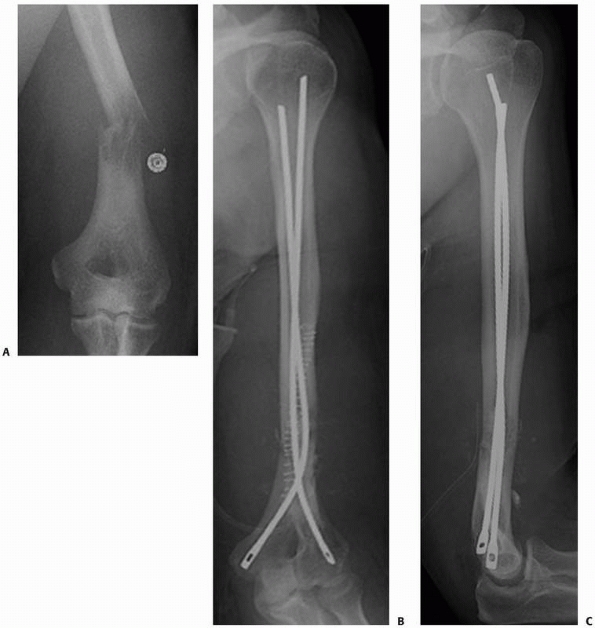

FIGURE 20-6 A.

Anteroposterior radiograph of the left distal humerus in a 53-year-old-man with metastatic thyroid carcinoma. The osteolytic lesion was considered too distal for stabilization with an anterograde intramedullary nail. Internal fixation with dual plates is an option but would leave the remainder of the proximal humerus unprotected if future lesions occur. Anteroposterior (B) and lateral (C) postoperative radiographs demonstrate the reconstruction with flexible pins extending the length of the humerus. Curettage of the lesion was performed via a posterior approach, the humerus was intentionally shortened slightly for increased cortical contact, and methylmethacrylate was used to fill the defect after the fixation was placed. |